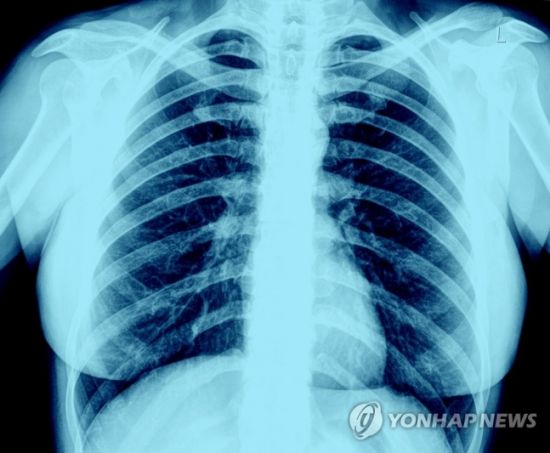

"엑스레이 촬영 결과 폐에서 짙은 상흔 발견"

14일(현지시간) 미 CBS 방송에 출연한 브리트니 뱅크헤드-켄들 텍사스 공대 박사는 "그동안 엑스레이 촬영 결과 코로나19 환자의 폐에서 짙은 상흔이 발견되지 않은 적이 드물었다"며 "애연가들과 비교해 상태가 더 나쁠 정도"라고 밝혔다.

켄들 박사 설명에 따르면 폐 상태가 안 좋을수록 엑스레이 상에 흰색 부분이 많이 드러난다. 정상적인 폐의 경우 엑스레이 사진은 대개 검은색인데, 이는 공기가 많이 들어가 있는 건강한 상태다.

그러나 애연가의 폐는 상흔·충혈 등 때문에 흰색 부위가 곳곳에 나타난다.

문제는 코로나19에 감염된 사람들의 폐다. 이들은 폐 전체가 거의 흰색으로 나오는 것으로 확인됐다.

심지어 무증상 감염자라고 해도 엑스레이 촬영 결과 폐에서 심한 상흔이 발견되는 비율은 거의 70~80%에 달한다고 켄들 박사는 덧붙였다.